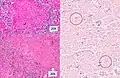

Histopathology, showing epithelioid granulomas with multinucleated giant cells and acid-fast bacilli